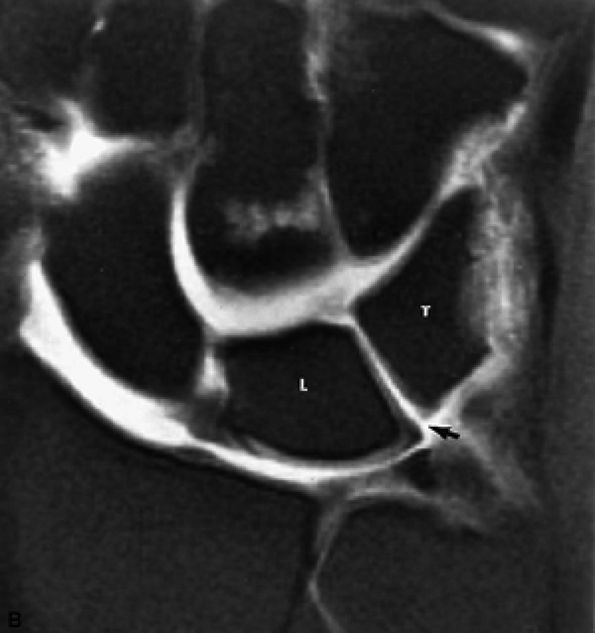

FIGURE 10.35 LUNOTRIQUETRAL LIGAMENT.

The lunotriquetral ligament is usually visualized as a thin horseshoe-shaped structure that may appear more lax than the scapholunate ligament on MR imaging.43 The lunotriquetral ligament does not extend as far distally into the lunotriquetral joint as the longer proximal distal portion of the scapholunate ligament does within the scapholunate joint.

The volar and dorsal portions of the lunotriquetral ligament attach directly to bone, whereas its midportion attaches to the hyaline articular cartilage of the lunotriquetral joint.43

Smith and Snearly53 have shown that on coronal MR images the lunotriquetral ligament is most commonly delta-shaped (triangular) or linear.

of both scapholunate and lunotriquetral ligament pathology. MR imaging is superior to conventional arthrography, allowing identification of the size, morphology, and location of a scapholunate or lunotriquetral ligament tear. This information is important because communication across a pinhole or small perforation or deficiency of the thin membranous portion of the ligament may not be significant in the presence of grossly intact dorsal and volar ligaments. In fact, evaluations of communicating perforations in cadaver wrists have shown that 28% of cadaver wrists have degenerative perforations of the central membranous scapholunate ligament.59 Degenerative perforations of the membranous lunotriquetral ligament can be seen in 36% of cadaver wrists. In our experience, degenerative perforations occur twice as often in the lunotriquetral ligament as in the scapholunate ligament.